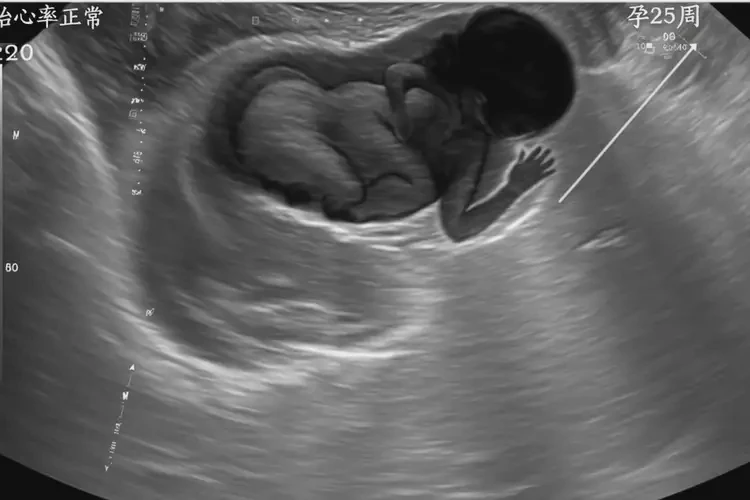

孕25周1天胎心率179有危險(xiǎn)嗎(圖1)